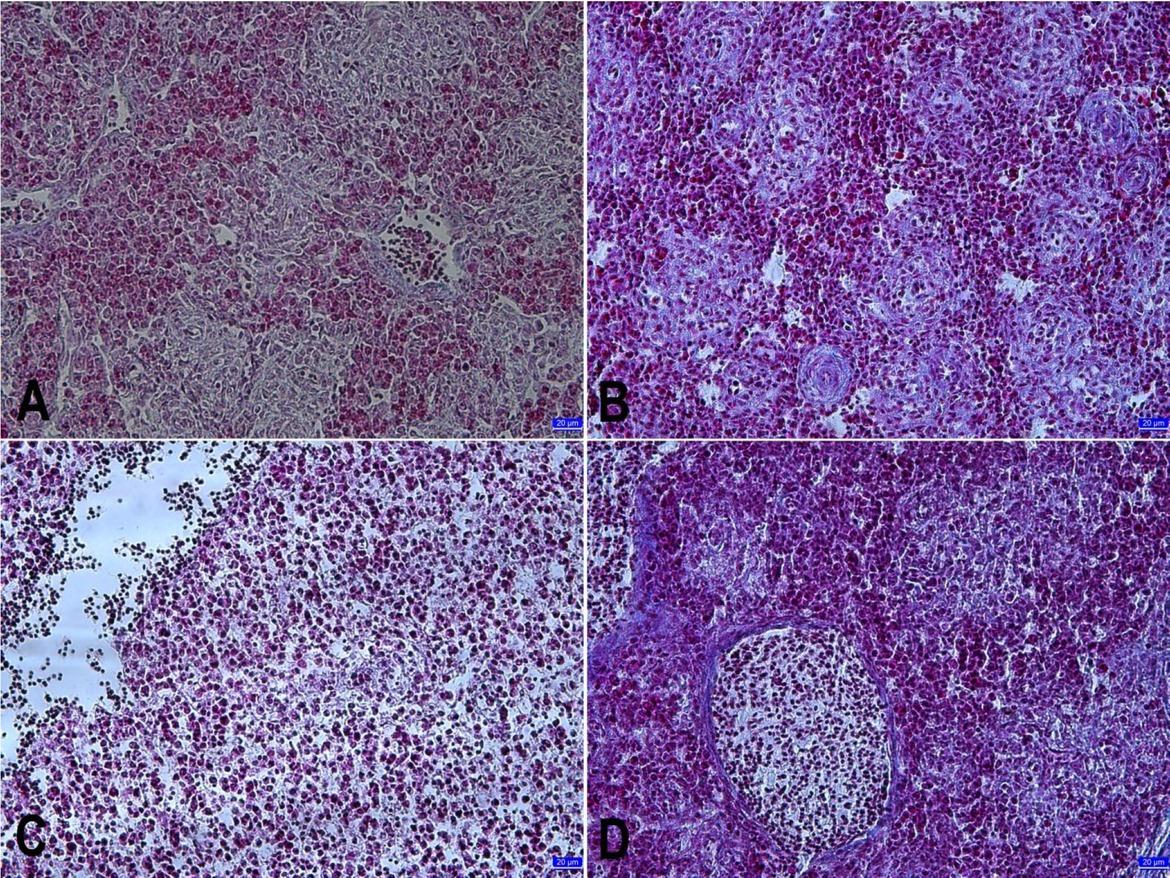

The microscopic evaluation of the thymus sections is presented in Fig. 3. The thymus sections of the control group had normal histological structure. On the 10th day of incubation, there were mostly mesenchymal cell communities. Large basophilic cells that are the precursors of small type lymphocytes were also detected in these areas. In the experimental groups, thymus development was suppressed to an extent dependent on the dose. The most significant changes were observed in the SY1,000 and SY2,000 groups. Cells that were small-type lymphocyte structures were not seen in these groups, while they were in the SY200 group. On day 13 of incubation, the lobule structure in the thymus drafts was prominent in the control group. In these lobules, dark and light stained areas were found. These areas were the cortex, which was rich in small-type lymphocytes, and the medulla, which was poor in these cells. A distinction between the cortex and medulla could be made in this incubation period. Vascularisation was observed to be advanced. When compared to the control group at this time, it was noted that the lobule structure of the thymus was less distinct and the vacuolation was weak in the SY1,000 and SY2,000 groups. The number of small-type lymphocytes also decreased with increasing doses. Cortex–medulla distinction could not be made in these groups. When incubation had taken place for 16 days, the cortex–medulla distinction was more evident in the thymus lobules of the control group. The cortex was dense in small-type lymphocytes. Large blood vessels were seen in the interlobular connective tissue. The most notable change in the SY1,000 and SY2,000 groups was pronounced developmental retardation, seen in small lobule structure, uncertain cortex–medulla separation, poor vascularisation, and undeveloped interlobular connective tissue. On the 21st day, it was determined that the thymus of the control group had completed its development. The capsule surrounding the organ, developed interlobular connective tissue, a prominent cortex–medulla border, developed vascularisation, dense lymphocytes accumulation in the cortex, and Hassall’s corpuscles were found. When compared to the control group, the developmental retardation of the thymus was apparent proportional to the doses in the treatment groups. Developmental retardation was most clearly observed in the SY1,000 and SY2,000 groups.

Fig. 3

Light microscopic images of the thymus sections in different embryonic periods. A – the thymus section from a day 10 chick embryo in the control group; B – the thymus section from a day 21 chick embryo treated with SY200; C– the thymus section from a day 21 chick embryo treated with SY1,000 showing Hassall’s corpuscles; D – the thymus section from a day 21 chick embryo treated with SY2,000